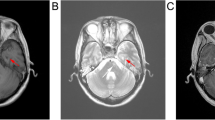

A total of 8 cases (8/327) developed MRI-indicated radiotherapy-induced brainstem injury. The actuarial incidence rates were 2.2% and 2.8% at 3 and 5 years, respectively; and these were 2.5% and 5.3% in T3 and T4 patients, respectively (Fig. 1). The median latency period was 21 months (range, 9–58 months).

Overall, the MRI findings in the brainstem injury patients revealed a continuous spectrum of RT-associated damage. Small solid enhanced nodules were evident in four cases, while moderate and large lesions were apparent in other cases (lesions were classified as described in Table 1). The evolution of radiotherapy-induced brainstem injury was well documented; the MRI features of brainstem injury (including signal abnormality on T1 and T2 images) resolved completely in three patients following gradual improvement over two months. However, one patient developed a large contrast-enhanced lesion, with a central necrotic core in the base of the pons; this was the only patient with brainstem injury who died (Fig. 2).

Necrosis nidus within the brainstem and the corresponding dose distribution. Contrast-enhanced lesion (white arrow) in the axial (a) and sagittal (c) view on post-contrast T1-weighted MRI images with a 53-year-old NPC patient (the 5th patient in Table 1). Corresponding isodose lines are shown in b and d, respectively